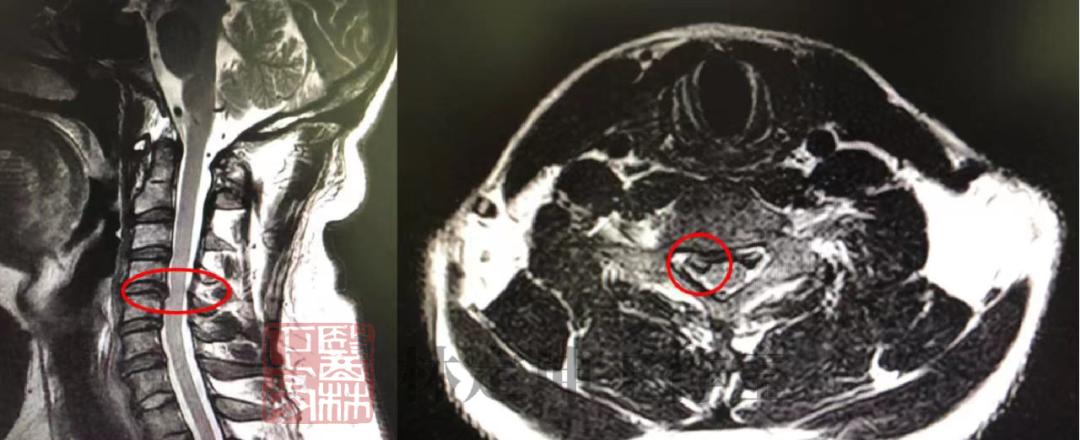

二、椎间盘突出

“椎间盘突出”,影像学报告中的又一常见词汇,也是让很多患者绕进治疗弯路的开始。

一字之差,方法不同!

1、椎间盘突出,要养

椎间盘从25岁左右就开始进入自然退变的过程,到了一定年龄,颈腰椎间盘都会多少有点突出,只要突出尚 在正常范围内 的,没有引起不适,就可以 不必采取治疗措施 ,而是要采取养护措施,例如少低头,少弯腰,注意好防寒保暖等。

2、椎间盘突出症,治养结合

突出的同时,伴随腰腿不舒服的情况,则一定要及时前往专科,找专业的医生进行针对性地治疗,切勿轻信各种偏方,以免适得其反。同时,日常生活中也要做好养护措施,避免再次诱发病症或导致病症加重。

四、椎体血管瘤

拍片发现椎体长瘤子了?!

1、体积小,不必担忧

长在椎体的血管瘤,一般都是非常小,且生长速度是比较缓慢的,也不会引起疼痛, 不用做任何特殊处理 ,同时其属于良性肿瘤,不会癌变,因此大家不必过于担忧。

2、体积大,需干预治疗

除非是个别血管瘤体积特别大,超过了 椎体的二分之一 ,对椎体的刚度产生影响,可能会引起疼痛,这时候就需要采取相应的治疗措施。即便要做手术,填充一点骨水泥进去也就能治好了。